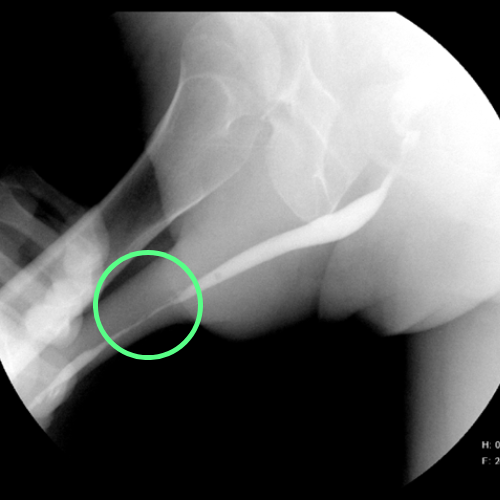

Imagen de cistouretrografía con referencias que permiten identificar un segmento uretral con calibre normal y uno con calibre reducido.

Cistouretrografía que revela una estenosis de uretra. El asterisco (*) marca una porción de uretra con calibre normal, mientras que el círculo un segmento más estrecho.